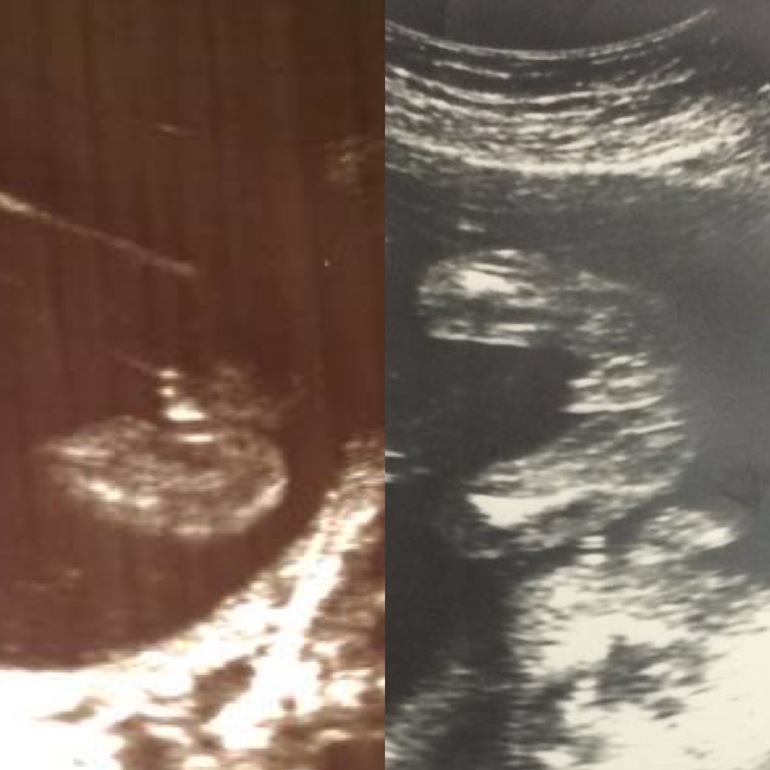

Ольга Михайлова в Здоровье будущей мамы 9 лет Привет девушки! Как думаете, какой пол? 18 недель Результаты: УЗИ, КТГ, доплера, скрининга Посмотрите еще 20 записей на эту тему Отменить Ответить Ольга Михайлова Спасибо за ответы) узист сказала, скорей всего девочка 23.01.2017 Ответить Матильда Похожа на девочку,а узистка что сказала? вот мальчик 👦 23.01.2017 Ответить Юлия Ч Похоже на девочку. 23.01.2017 Ответить Дарья Мне кажется мальчик! 22.01.2017 Ответить Anastasia Как по мне, так больше на девочку похоже.. вот в сравнении (справа мальчик). 22.01.2017 Ответить Евгения 50 на 50) 22.01.2017 Ответить Виктория по мне так мальчик 22.01.2017 Ответить Доплер - нууууу я прям растерялась... короткая шейка на 21 неделе. Чаты Беременных Выберите чат: Январята-2026 Февралята-2026 Мартята-2026 Апрелята-2026 Майчата-2026 Июнята-2026 Июлята-2026 Августята-2026